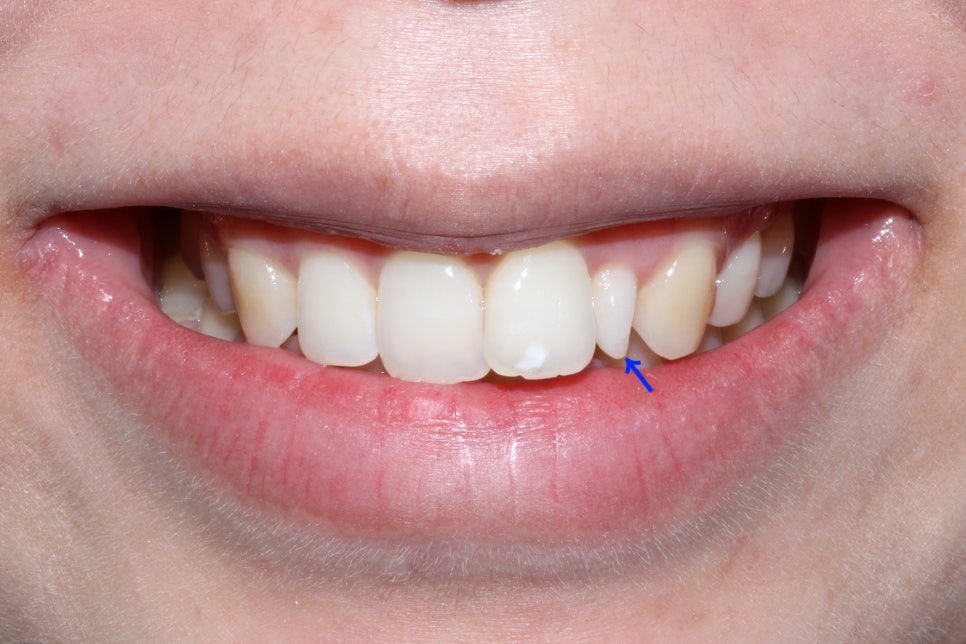

신논현역치과 뻐드렁니 case의 구외 사진입니다.

교정 전 입술과 입 주변의 형태를 보면

좌우의 대칭이 잘 맞지 않고 돌출된 느낌이 있는 모습인데요,

상악 좌측 측절치가 왜소치 증상이 있고

앞니(중절치)가 주변 치열보다 뻐드러져 있어

입술을 다물었을 때도 돌출감이 느껴지는 모습입니다.

특히 스마일라인의 치아가 측절치 및 탈회가 있는

중절치로 인해 심미성이 떨어져 보이기 때문에

교정 및 보철치료를 통해 이를 보완하려고 하는데요,